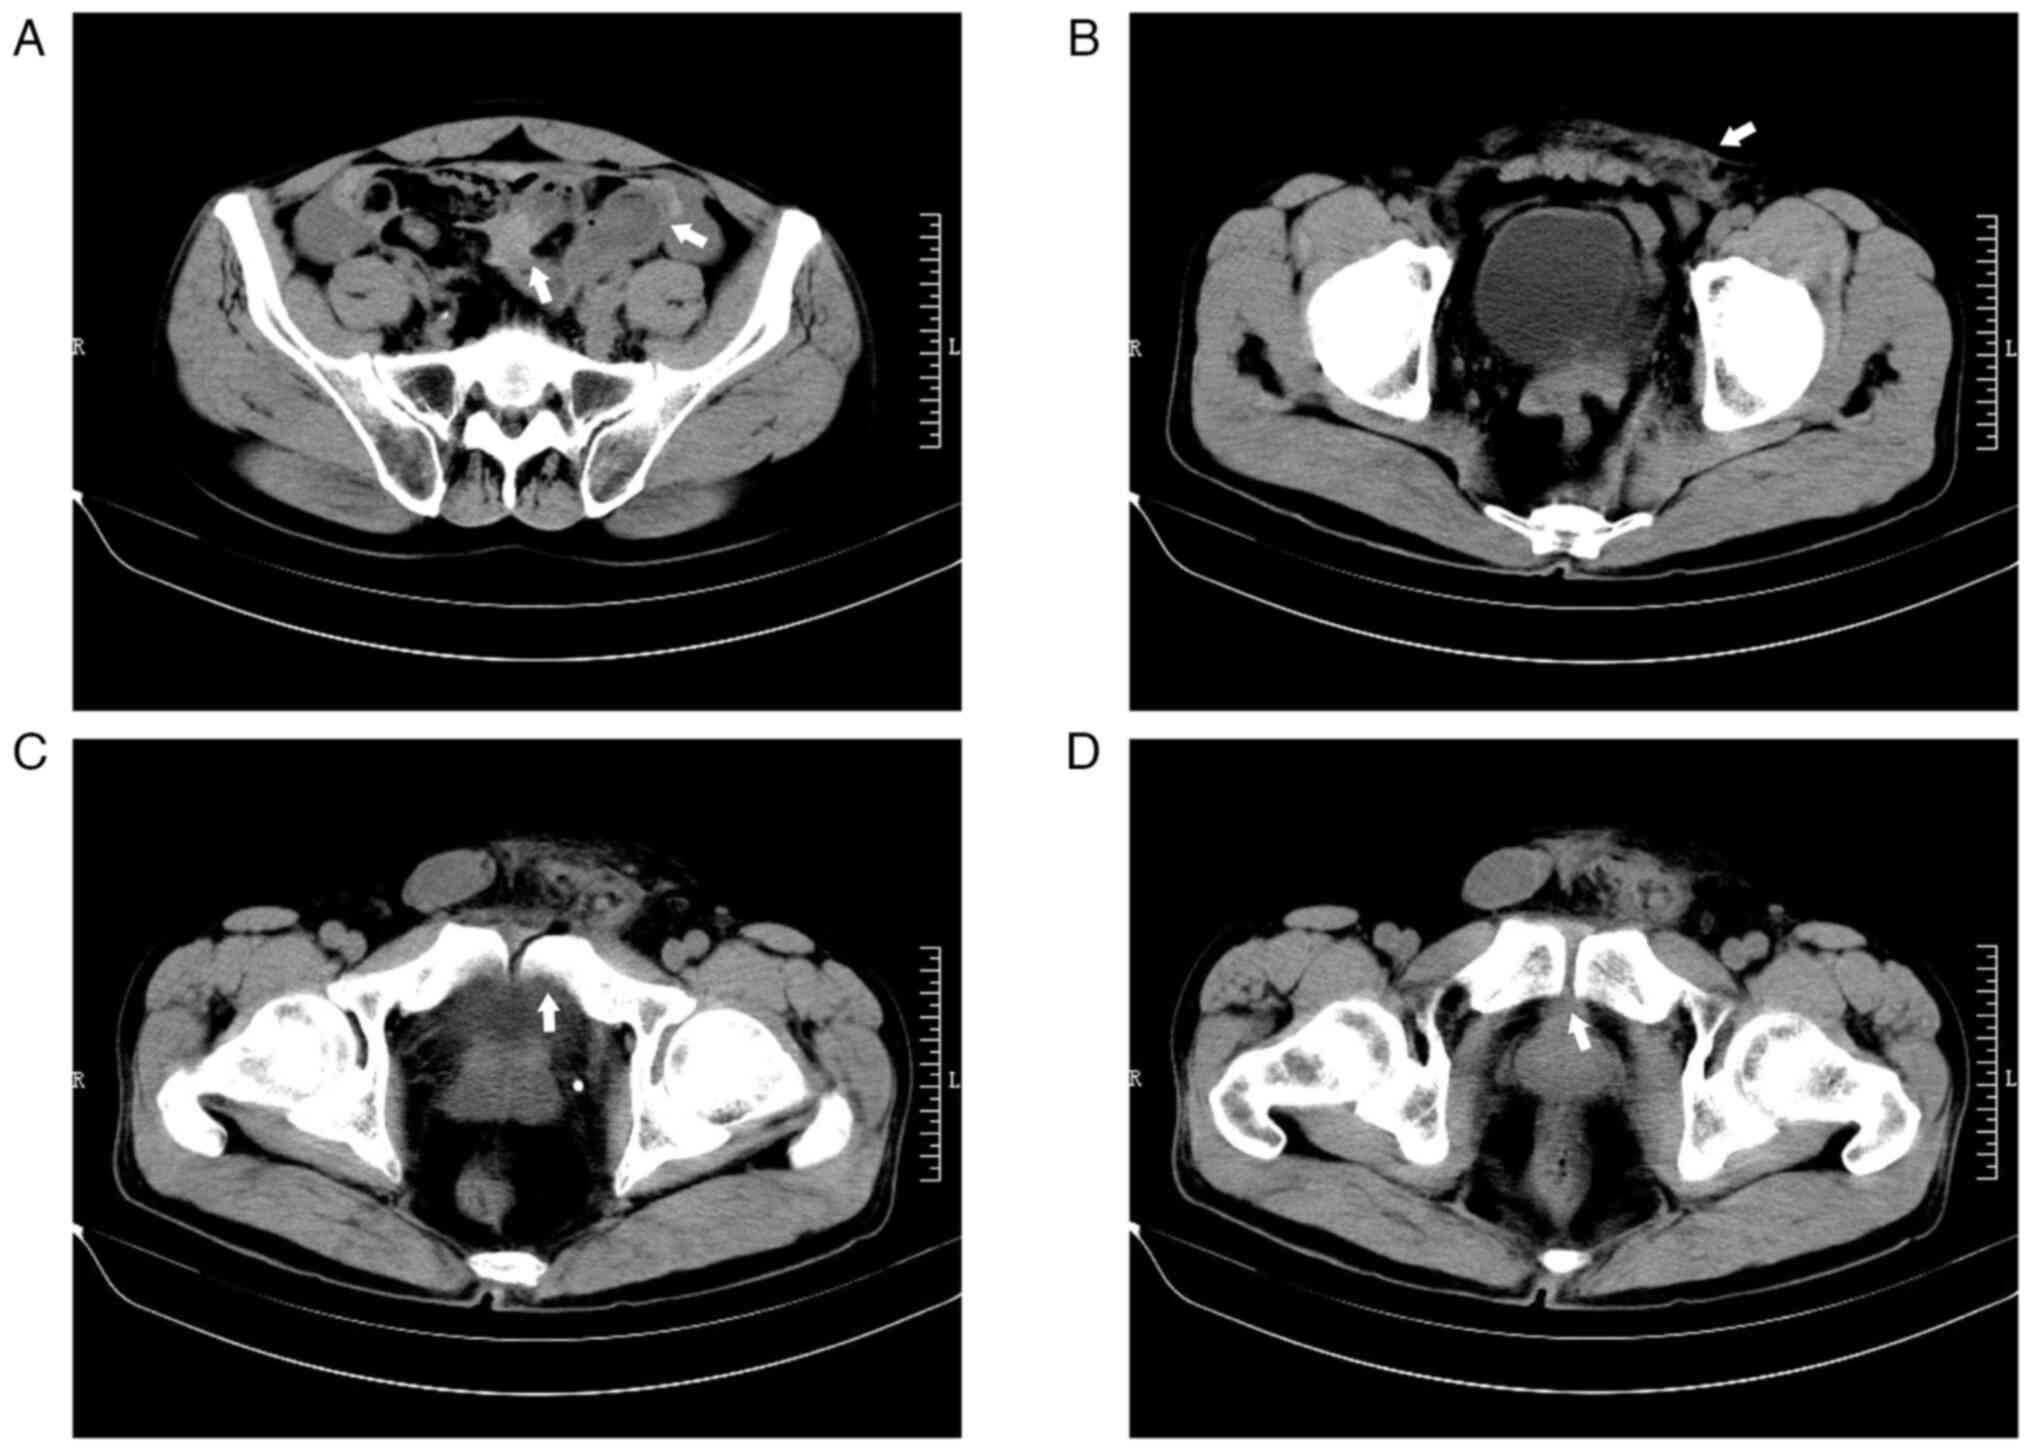

Secondary bladder stone caused by delayed penetration of the bladder by a pubic fracture: A case report and literature review

Pelvic fractures sometimes lead to injuries of the urinary bladder, which commonly present as gross hematuria, dysuria and lower abdominal pain. As a type of urinary stone, bladder stones are usually secondary to lower urinary tract obstruction, such as benign prostatic hyperplasia, urethral stricture, and neurogenic bladder. The present case report examines an unusual case of a delayed pubic fracture penetrating the bladder, which caused a secondary bladder stone. A 53-year-old man was first hospitalized at The Second Hospital of Jiaxing (Jiaxing, China) in January 2020 because of trauma-induced bleeding in the scalp and abdominal pain. The patient underwent abdominal exploration and partial bowel resection, and his condition stabilized after surgery. After discharge, the patient had regular outpatient check-ups every 2-3 weeks. However, after 3 months, in April 2020, the patient was readmitted to the hospital because of frequent urination, an urgent need for urination and dysuria. Abdominal computed tomography imaging and cystoscopy revealed a pubic fracture that had penetrated the bladder wall, accompanied by a bladder stone. Subsequently, cystolithotomy was performed, which provided significant relief of symptoms once the catheter was removed after 2 weeks. Since then, the patient has been followed up until January 2023 and had remained asymptomatic. Bladder stones caused by necrotic bone fragmentation are rare. Bladder injuries resulting from pelvic fractures can have delayed onset; therefore, clinicians should be aware of the possibility of urogenital injury in such patients. It is crucial for clinicians to comprehend the potential mechanisms involved, analyze the clinical data of patients, closely monitor their condition and implement appropriate treatment measures when necessary.